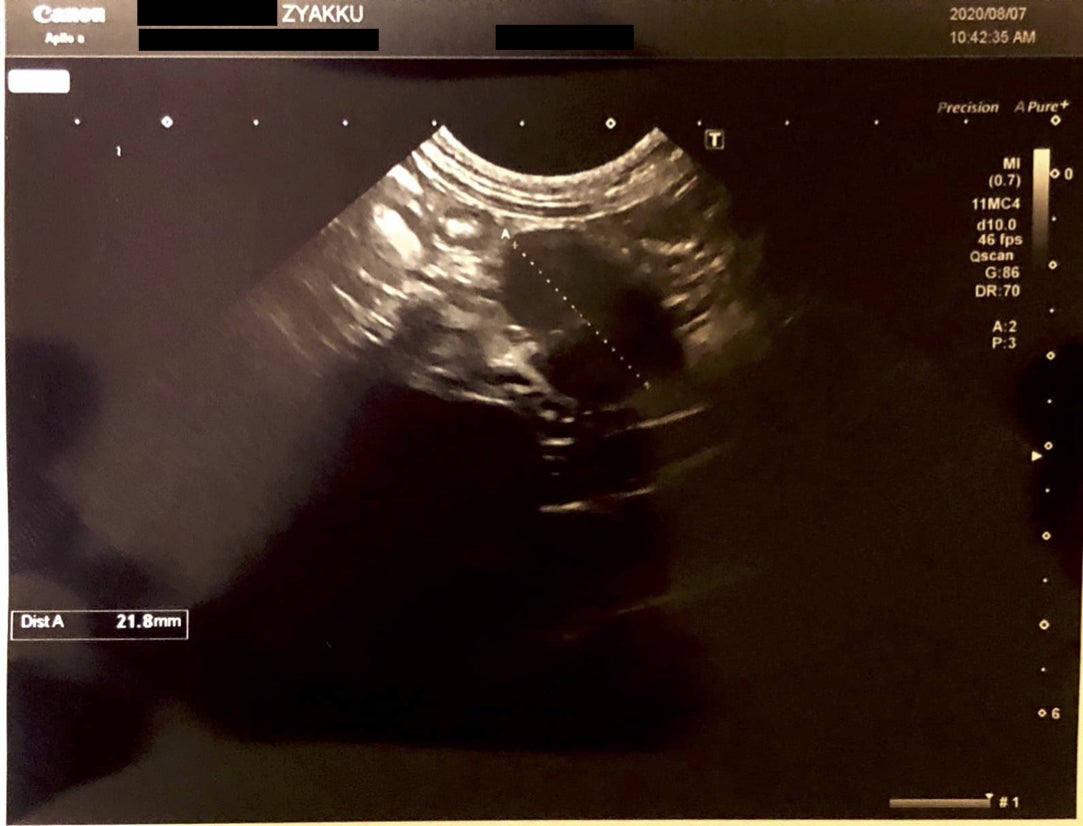

2020/8/1 血液検査後、身体の中をエコー検査。

エコー検査では、身体の内部に2cmほどの腫瘍が確認。

年齢、血液検査、エコー検査を総合した診断結果は、FIPの可能性が高いとのこと

到着後、再度、診察では血液検査、エコー検査をいたしました。

血液検査では、前回と変わらず、白血球の数値が高い、総タンパク質が高い、SAA(血清アミロイドA)もステロイドを飲んでいるにもかかわらず高い。

エコーで調べた身体の内部には、腸内に2cmの腫瘍がありました。

やはりFIPの可能性が高いとのことでした。

念のため腫瘍部分に注射を入れ成分を抽出し、検査を出すことにいたしました。